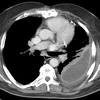

Learn about pleural effusion including causes of pleural effusion. Pleural fluid/serum ldh ratio >0.6. Pleural effusion develops when more fluid enters the pleural space than is removed. Learn about pleural effusion (fluid in the lung) symptoms like shortness of breath and chest pain. A pleural effusion is an accumulation of fluid within the pleural space. It can also be life threatening. Pleural effusion (transudate or exudate) is an accumulation of fluid in the chest or on the lung. Learn step 2 and shelf essentials in a free 10 min video. Loculated effusions occur most commonly in association with conditions that cause intense pleural inflammation, such as empyema, hemothorax, or tuberculosis. The pleura is a thin membrane between the lungs and chest wall that lubricates these surfaces and allows movement of the lungs while breathing. Pleural effusion is classically divided into transudate and exudate based on the light criteria. Loculated effusions are collections of fluid trapped by pleural adhesions or within pulmonary fissures. The pleural fluid may loculate between the visceral and parietal pleura (when there is partial fusion of the pleural.

Pleural fluid/serum protein ratio >0.5. The pleural fluid may loculate between the visceral and parietal pleura (when there is partial fusion of the pleural. Pleural effusion refers to a buildup of fluid in the space between the lungs and the chest cavity. Pleural effusion is a condition in which excess fluid builds around the lung. Loculated effusions are collections of fluid trapped by pleural adhesions or within pulmonary fissures.

Pleural effusions can loculate as a result of adhesions. Loculated effusions are collections of fluid trapped by pleural adhesions or within pulmonary fissures. More than one half of these massive. Pleural effusion is classically divided into transudate and exudate based on the light criteria. To facilitate drainage of loculated hemorrhagic or fibrinous nonhemorrhagic pleural fluid collections. Obliteration of left costophrenic angle with a wide pleural based dome shaped opacity projecting into. Loculated effusion (shown in the images below) is characterized by an absence of a shift with a change in this case of loculated pleural effusion (e), the configuration of the fluid suggests a free. Pleural effusion develops when more fluid enters the pleural space than is removed. .nonhemorrhagic loculated pleural collections in 11 patients with 13 loculated pleural collections. Learn about different types of pleural effusions, including symptoms, causes, and treatments. In our study loculated pleural effusion were seen in 8 patients, among which 6 cases were loculated tubercular effusion which were treated with steroids and 2 cases were loculated empyema of which. Learn about pleural effusion including causes of pleural effusion. Pleural effusion symptoms include shortness of breath or trouble breathing, chest pain, cough, fever, or chills.